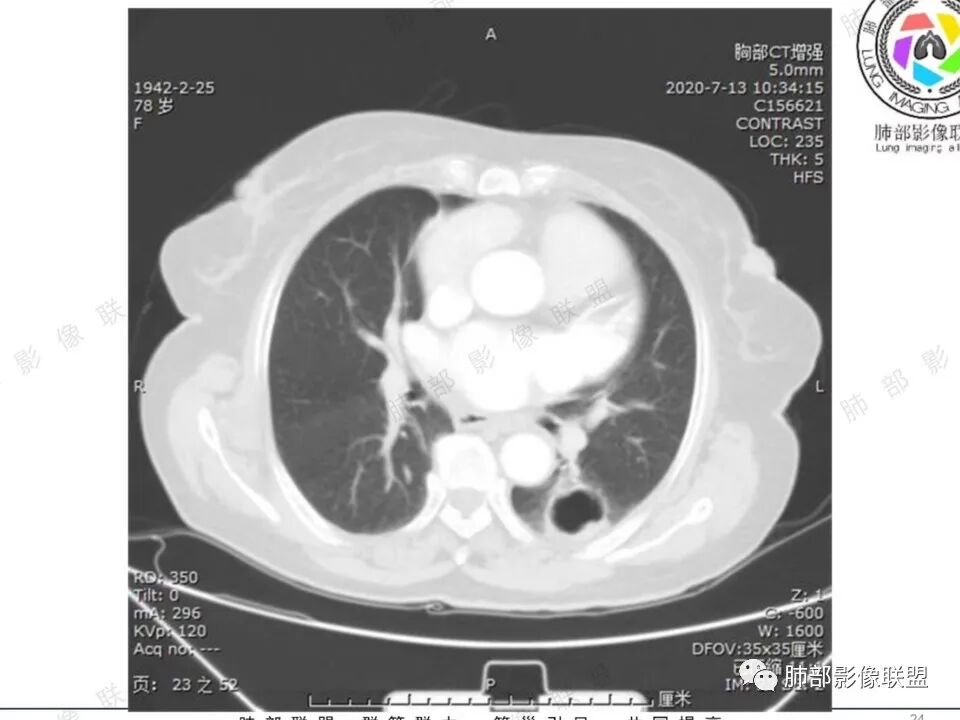

穿越七海的风: 右肺下叶不规则结节伴空洞,似鬼脸,壁厚度不均,壁内结节,首先考虑恶性,既往甲状腺癌病史,不除外转移。

蔡笑燕: 右肺不规则实性囊腔结节,囊腔内有血管走形和分隔,有分叶,细短毛刺,周围有清晰磨玻璃,胸膜牵拉,考虑IAC。

看图说话: 不规则结节,假大空,壁结节,边缘收缩,胸膜牵拉,周围有分叶,毛刺,伴有清晰磨玻璃影,周围有小结节,考虑肺腺癌,鉴别:1:结核,2,隐球菌。

哦落花时节 (刘朋): 中青年男性,右肺下叶不规则结节,内见多发囊腔,囊腔内壁不光滑,邻近叶间裂明显局部凹陷,有胸膜牵拉,血管聚集,考虑囊腔性腺癌,鉴别转移。

清茶: 青年男性,右肺下叶高密度结节影,有毛刺、分叶,内见空洞,边界尚清,考虑恶性,腺癌可能。

王秀仙: 右下肺 囊腔性结节,囊壁不均匀增厚,壁结节,毛刺分叶,胸膜凹陷,周边有边界清楚磨玻璃影,考虑囊腔型肺癌,腺癌。

心灵鸡汤: 青年男性,有甲状腺癌穿刺活检病史, 右肺下叶不规则囊腔,内壁不光整,似见壁结节,偏远侧见实性结节,病灶边缘可见分叶,毛刺,邻近血管支气管走行不自然,邻近斜裂牵拉,考虑二元,恶性结节,腺癌可能性大,转移、结核待排。